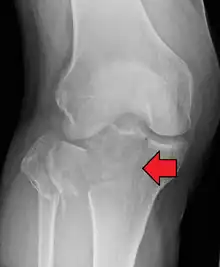

Lipohemarthrosis (presence of fat and blood from bone marrow in the joint space after an intraarticular fracture) seen on X-ray in a person with a subtle tibial plateau fracture

Lipohemarthrosis due to a tibial plateau fracture

Subtle tibial plateau fracture on an AP X ray of the knee

A tibial plateau fracture seen on X-ray